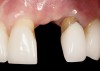

Fig 4. Intraoral view of tooth No. 7 with the gingival zenith more apical than the adjacent central incisor and canine tooth.

Figure 4

Problem: The implant is placed too facially, and there is significant labial gingival recession, contour change, and mucosal discoloration around the implant, abutment, and crown (Figure 3 and Figure 4). The implant attachment apparatus is intact and healthy, but the patient has a thin periodontal phenotype.

The following case report provides an example of this case scenario: A 28-year-old white female patient presented with her maxillary right lateral incisor significantly longer than the contralateral tooth following restoration of an existing crown that was 10 years old (Figure 3). The patient was dissatisfied with the esthetic appearance of the restoration due to the increased length, recession of the gingival tissues, and discoloration of the surrounding mucosa (Figure 4). Similar to case scenario No. 1, the first step in treatment was to decoronate the healthy implant by placing a flat surgical cover screw and employing a provisional resin-bonded-retained (RBR) prosthesis as a transitional fixed restoration (Figure 5 and Figure 6). The gingival augmentation in situ was allowed to take place for 2 to 3 weeks and was evaluated after that time (Figure 7).